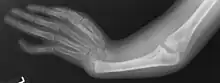

Radial ray malformations

This is characterized by hand and arm abnormalities. The following are specific characteristics:

- Malformed or absent (aplasia) thumb

- A thumb that looks more like a finger

- Partial or complete absence of a radius

- Shortening and radial deviation of the forearms

- Triphalangeal thumb

- Duplication of the thumb (preaxial polydactyly)

- Radial ray malformations

- Malformed, absent, or extra thumb

- A thumb that looks more like a finger

- Duplication of the thumb (preaxial polydactyly)

- Deformity of the arm due to a lack of the radius

- Surgery for correction of severe malformations of the forearms

- Construction of a functional thumb via surgery if aplasia of the thumb is present